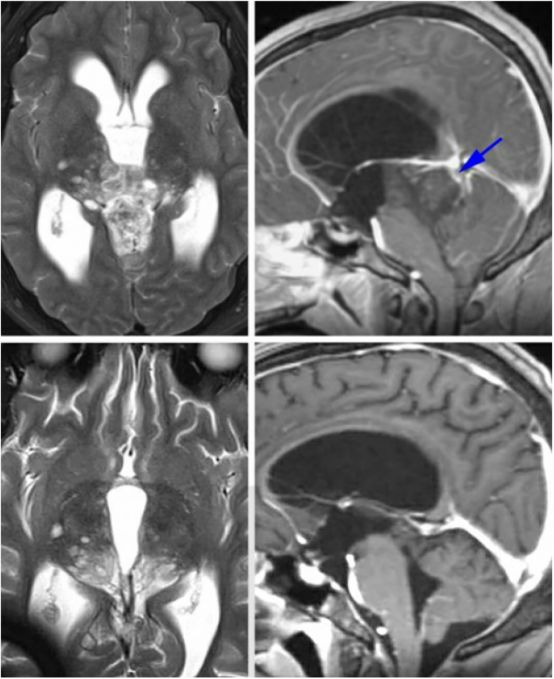

图2. 各种类型的松果体区病变。上排所示为一例松果体囊肿,注意其只有薄层环形强化;下排所示为一例顶盖区毛细胞型星形细胞瘤;而其他病变,如生殖细胞瘤、松果体母细胞瘤和胶质瘤卒中请阅读Selection of Operative Corridor章节。

图4. 对于有些患者,术前仔细评估深部静脉系统是有好处的。如图所示为一例未成熟畸胎瘤患者,术前CT血管成像提示大脑大静脉及其属支位于肿瘤后方(蓝色箭头)。这种静脉结构使得我们不能采用显露更好的小脑上入路,而枕部经天幕入路更为合适。

图19. 这是一例顶盖区的低级别星形细胞瘤(上图),术前影像提示大脑大静脉在肿瘤后方(上图,右,蓝色箭头所指)。尽管笔者术中在处理肿瘤时保持对寻找该静脉的高度警惕,但仍然差点损伤它,因为它嵌入了肿瘤中。术后影像(下图)提示肿瘤次全切,这点如术前计划的一样,肿瘤在丘脑内的部分残留。该病例也再次强调了仔细分析术前影像的重要性。